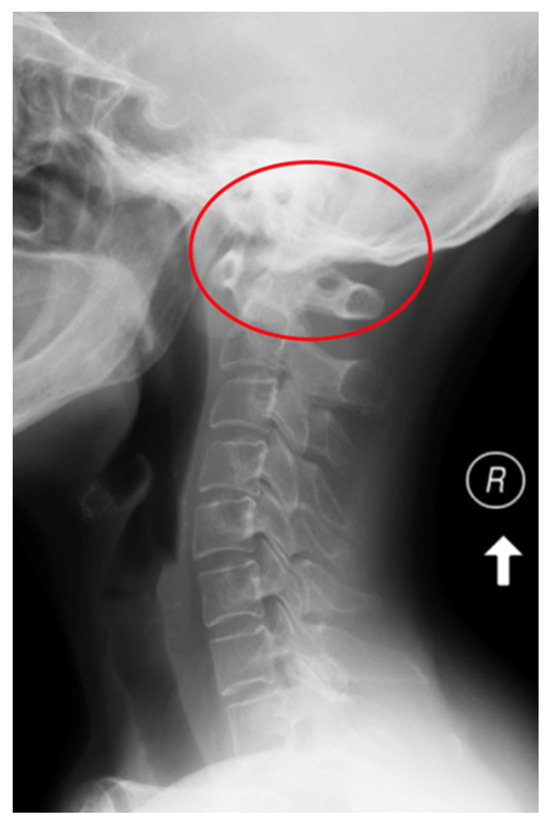

| AAS (atlantoaxial subluxation) | Weakening or rupture of ligaments and subchondral bone erosion in the atlantoaxial C1–C2 joints. |

| SAS (subaxial subluxation) | Subluxation in the joints C2–C7 due to destruction of the joint surface and the ligaments between the processes spinosis. |

| CS (cranial settling) | Vertical translocation of dens C0–C2 into the foramen magnum. |